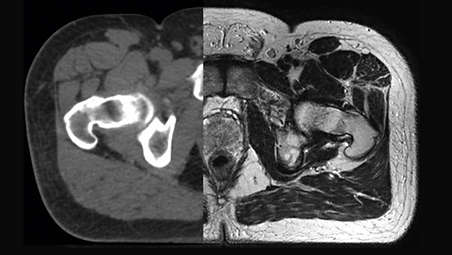

Our innovative MRCAT (MR for Calculating ATtenuation) clinical applications lets you plan radiation therapy using MRI as primary imaging modality. Within just one, fast MR exam, MRCAT provides both excellent soft-tissue contrast for target and OAR delineation and CT-like density information for dose calculations. This not only extends the benefits of MRI’s excellent soft-tissue contrast to radiotherapy planning, but it also eliminates arduous, error-prone CT-MRI registration from the process, reducing uncertainties and complexity. Check out the related product section for the clinical application areas.

Our innovative MRCAT (MR for Calculating ATtenuation) clinical applications lets you plan radiation therapy using MRI as primary imaging modality. Within just one, fast MR exam, MRCAT provides both excellent soft-tissue contrast for target and OAR delineation and CT-like density information for dose calculations. This not only extends the benefits of MRI’s excellent soft-tissue contrast to radiotherapy planning, but it also eliminates arduous, error-prone CT-MRI registration from the process, reducing uncertainties and complexity. Check out the related product section for the clinical application areas.

Our innovative MRCAT (MR for Calculating ATtenuation) clinical applications lets you plan radiation therapy using MRI as primary imaging modality. Within just one, fast MR exam, MRCAT provides both excellent soft-tissue contrast for target and OAR delineation and CT-like density information for dose calculations. This not only extends the benefits of MRI’s excellent soft-tissue contrast to radiotherapy planning, but it also eliminates arduous, error-prone CT-MRI registration from the process, reducing uncertainties and complexity.

MRCAT Brain

- MR-only sim for primary and metastatic tumors in the brain

- Single-scan approach

- Automatic generation of synthetic CT images using AI

- Accuracy in dose planning

MRCAT Pelvis

- MR-only sim for pelvic radiotherapy planning

- Robust, consistent imaging protocol

- Continuous Hounsfield units

- Accuracy in dose planning

MRCAT Brain

MRCAT Brain clinical application allows the use of MRI as the primary imaging modality for radiotherapy planning of primary and metastatic tumors in the brain without the need for CT. Detailed anatomical information for contouring and attenuation maps for dose calculations are both obtained from a single, submillimeter resolution 3D T1W mDIXON MR sequence. Artificial Intelligence (AI) is used for fast computation of continuous Hounsfield units directly on the MR console.

MRCAT Pelvis

MRCAT Pelvis lets you plan radiation therapy using MRI as a single modality solution. Within just one MR exam, MRCAT Pelvis provides excellent soft-tissue contrast for target and OAR delineation, and continuous Hounsfield units for dose calculations. MRCAT (MR for Calculating ATtenuation) data can be used for export to treatment planning systems for CT-equivalent** dose calculations. In addition, MR-based imaging enables CBCT-based positioning based on soft-tissue contrast with the look and feel of CT.

Visa produkt